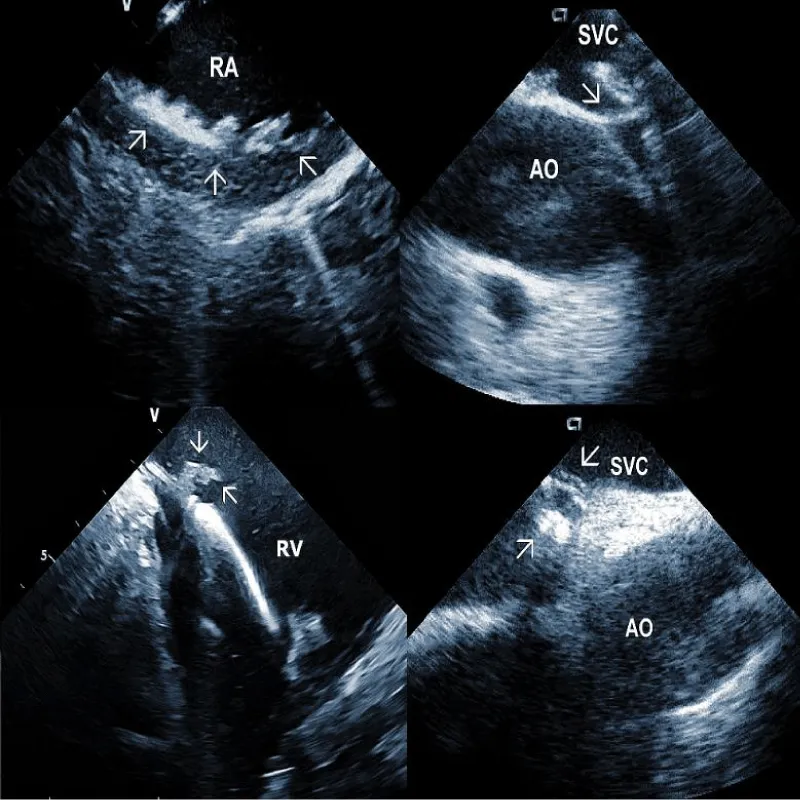

Lead adherent echo densities (LAE): ICE allows visuali-zation of the leads and echo densities adherent to them. In our experience, LAE can be detected in the majority of patients (Figure 2A). One recent study revealed LAE in 72% of cases [10]. Locations of LAE were the superior vena cava (16%), its junction with the right atrium (11%), right atrium (57%), and tricuspid annulus (16%). Finding LAE opens the question of their clinical importance. Interestingly, Ho, et al. systematically performed TEE before TLE, which was performed for non-infectious indications in 108 consecutive patients [11]. The authors reported an 18.5% incidence of lead thrombi, all of which were < 2 cm. This figure is significantly less than in the above study. This discrepancy can be explained by the higher resolution and superior maneuverability of ICE compared to TEE [12].

Areas of fibrous adherence: Areas of fibrous adherences or attachments (i.e., scar tissue) can be visualized as echo-dense structures along the lead course (Figure 3A). Multiple leads are usually attached by fibrous tissue together (Figure 3B). The location of fibrous adherence can be anywhere in the course of the lead [7,10]. In a study by Bongiorni, et al. [7], scar tissue was noted by ICE in the subclavian vein, innominate vein, and the right ventricle in about 80%, 68%, and 68% of cases, respectively. Sadek, et al. [10] described attachments less frequently – only in 18/50 pts (36%), predominantly intracardiac. Anecdotal cases were reported on specific locations of adhesions, such as a vulnerable “stalk” attaching the papillary muscle to the RV endocardium [18]. Notably, the fibrous attachment presence correlated with the extraction procedure’s difficulty. These patients were more likely to have a “complex” extraction procedure. Subjects who did not have evidence of lead attachment were less likely to require the advancement of the extraction sheaths past the superior vena cava and less likely to require advanced extraction tools such as snares.

At the beginning of the procedure, ICE is introduced into the right ventricle to check and document possible pericardial effusion and left or right ventricular function. The course of the lead within the right ventricle is visible (Figure 1A). In addition, attachments of the right ventricular leads to cardiac structures could be seen, and the tip of the lead can be localized (Figure 1B).

From the right atrial position, the course of the lead (or leads) could be overlooked. This is the best view to observe the presence of tricuspid regurgitation and the existence and location of lead adherent echo densities (LAE). Positioning the catheter in the superior vena cava or higher enables assessment of the lead attachments or binding sites in this region. Subtotal or total vein occlusion could be detected at the same time.

Representative Figure: Illustrative examples of clinical utility of intracardiac echocardiography in transvenous lead extraction.